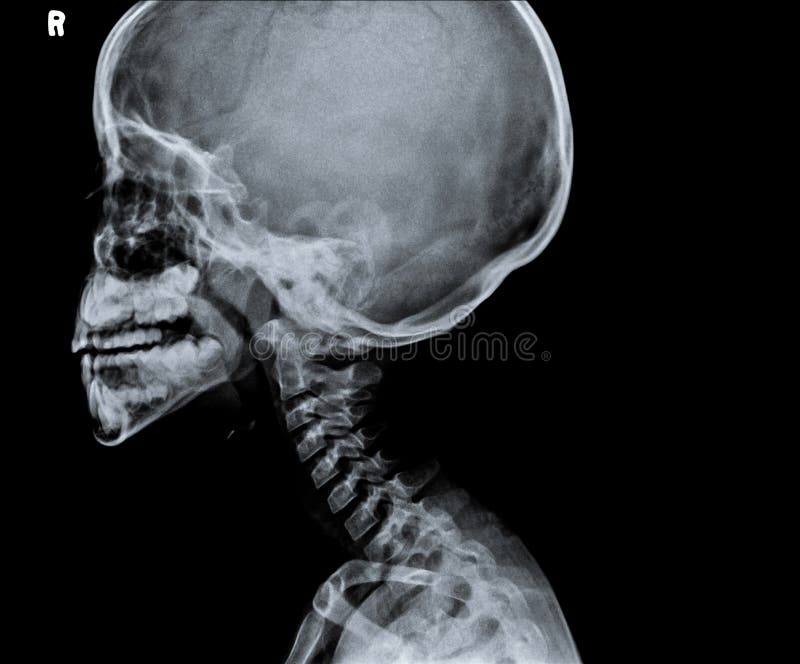

Radiografia Della Testa E Del Collo Foto Foto Stock Gratis E Royalty Free Da Dreamstime

Radiografia Della Testa E Del Collo Fotografia Stock Immagine Di Malattia Osso

La Radiografia Del Rachide Cervicale Umano E Della Testa Del Cranio Sella Turcica Sembra Normale Concetto Di Immagine Medica Foto Premium